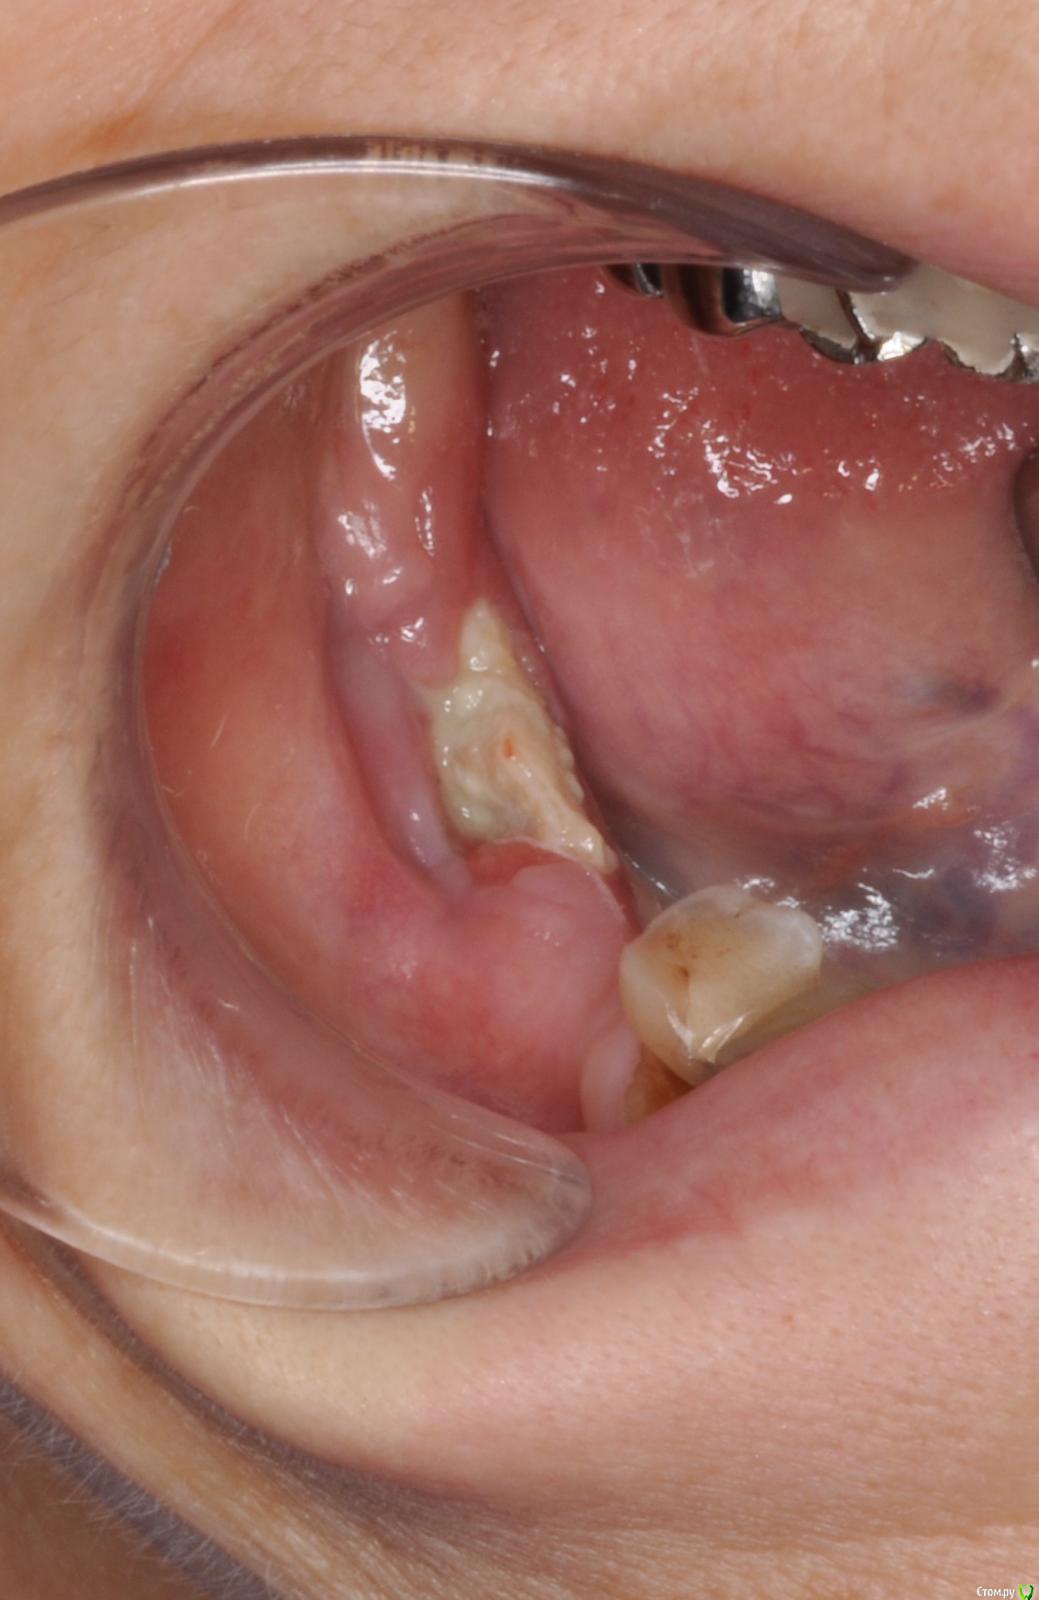

gum Опубликовано 5 апреля, 2017 Поделиться Опубликовано 5 апреля, 2017 Здравствуйте, обратилась пациентка, лет 7 назад тоже была на бисфосфонатах (онкология) года 4-5 назад удалены по одному зубу справа и слева, начался остеонекроз, с типичной картиной для таких случаев, потом она пропала и вот сегодня пришла, сделали кт, все видите сами, плюс наличие свищей, секвестры в полости рта. Вопрос: где в России или за ее пределами занимаются такими пациентами, куда ее направить для резекции и послед реконструкции? Ссылка на комментарий

kriokov Опубликовано 6 сентября, 2017 Автор Поделиться Опубликовано 6 сентября, 2017 пациентка 60 лет, бифосфонаты внутривенно в течении года , по поводу рака молочной железы, есть отдаленные метастазы. Обращалась ко мне 3 мес назад с просьбой удалить корни 46 и 47. Корни не болели , я отказал, но видать плохо обьяснил.Удалили в другом лпу, через месяц заболела челюсть, вылез очаг остеонекроза. Сейчас периодически болит, секвестрации полной нет, фрагмент не двигается, болит, яхык пока не режет. Лечение_ даже не знаю как сказать, назначил антисептики из разряда (меняйте пока хлоргекседи на бетадин, бетадин на перекись) и назначил после консультации с онкологом аугментин. Снимки решили с онкологом не делать, ей какое то жесткое обследование предстоит 3 Ссылка на комментарий

kriokov Опубликовано 10 октября, 2024 Автор Поделиться Опубликовано 10 октября, 2024 (изменено) Случай из практики , поделился коллега. Пациентке в 2019 году установлены имплантаты и НКР. В 2022 обнаружена злокачественная опухоль молочной железы. В дальнейшем метастазы в позвоночник, терапия , в том числе и бифосфонатами. Коллега делал осмотр и реннтгенографию в 2022, с его слов на снимках была убыль кости в области имплантата 37 на два витка. На сегодня жалобы пациентки- боли , особенно в вечернее время. Пациентка лечиться у онкологов с применением бифосфонатов. Изменено 10 октября, 2024 пользователем kriokov неправильно вставил ОПТГ Ссылка на комментарий